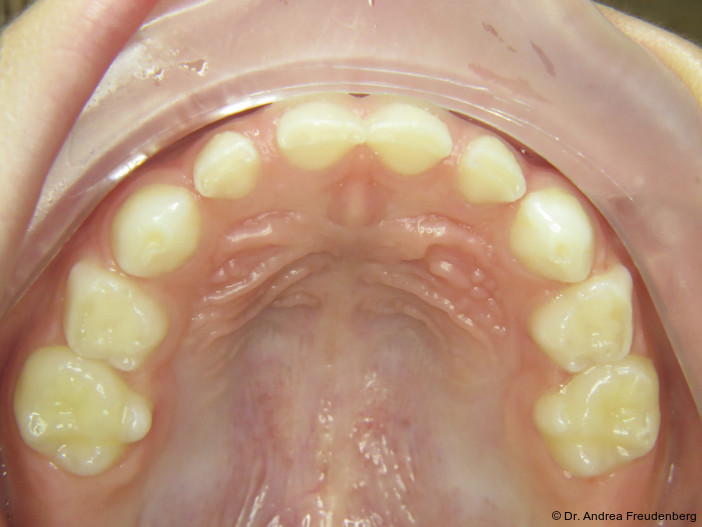

Da Pathologie, d.h. Fehlwachstum, allgegenwärtig ist, möchten wir kurz die physiologische Gebissentwicklung ins Gedächtnis zurückrufen. Ein physiologisches Milchgebiss sollte

- eine halbrunde Form der Zahnbögen,

- eine dezente sagittale und vertikale Frontzahnstufe und

- im Alter von vier bis fünf Jahren Lücken zwischen den Milchschneidezähnen aufweisen (die bleibenden Frontzähne sind ca. ein Drittel breiter als die Milchzähne).